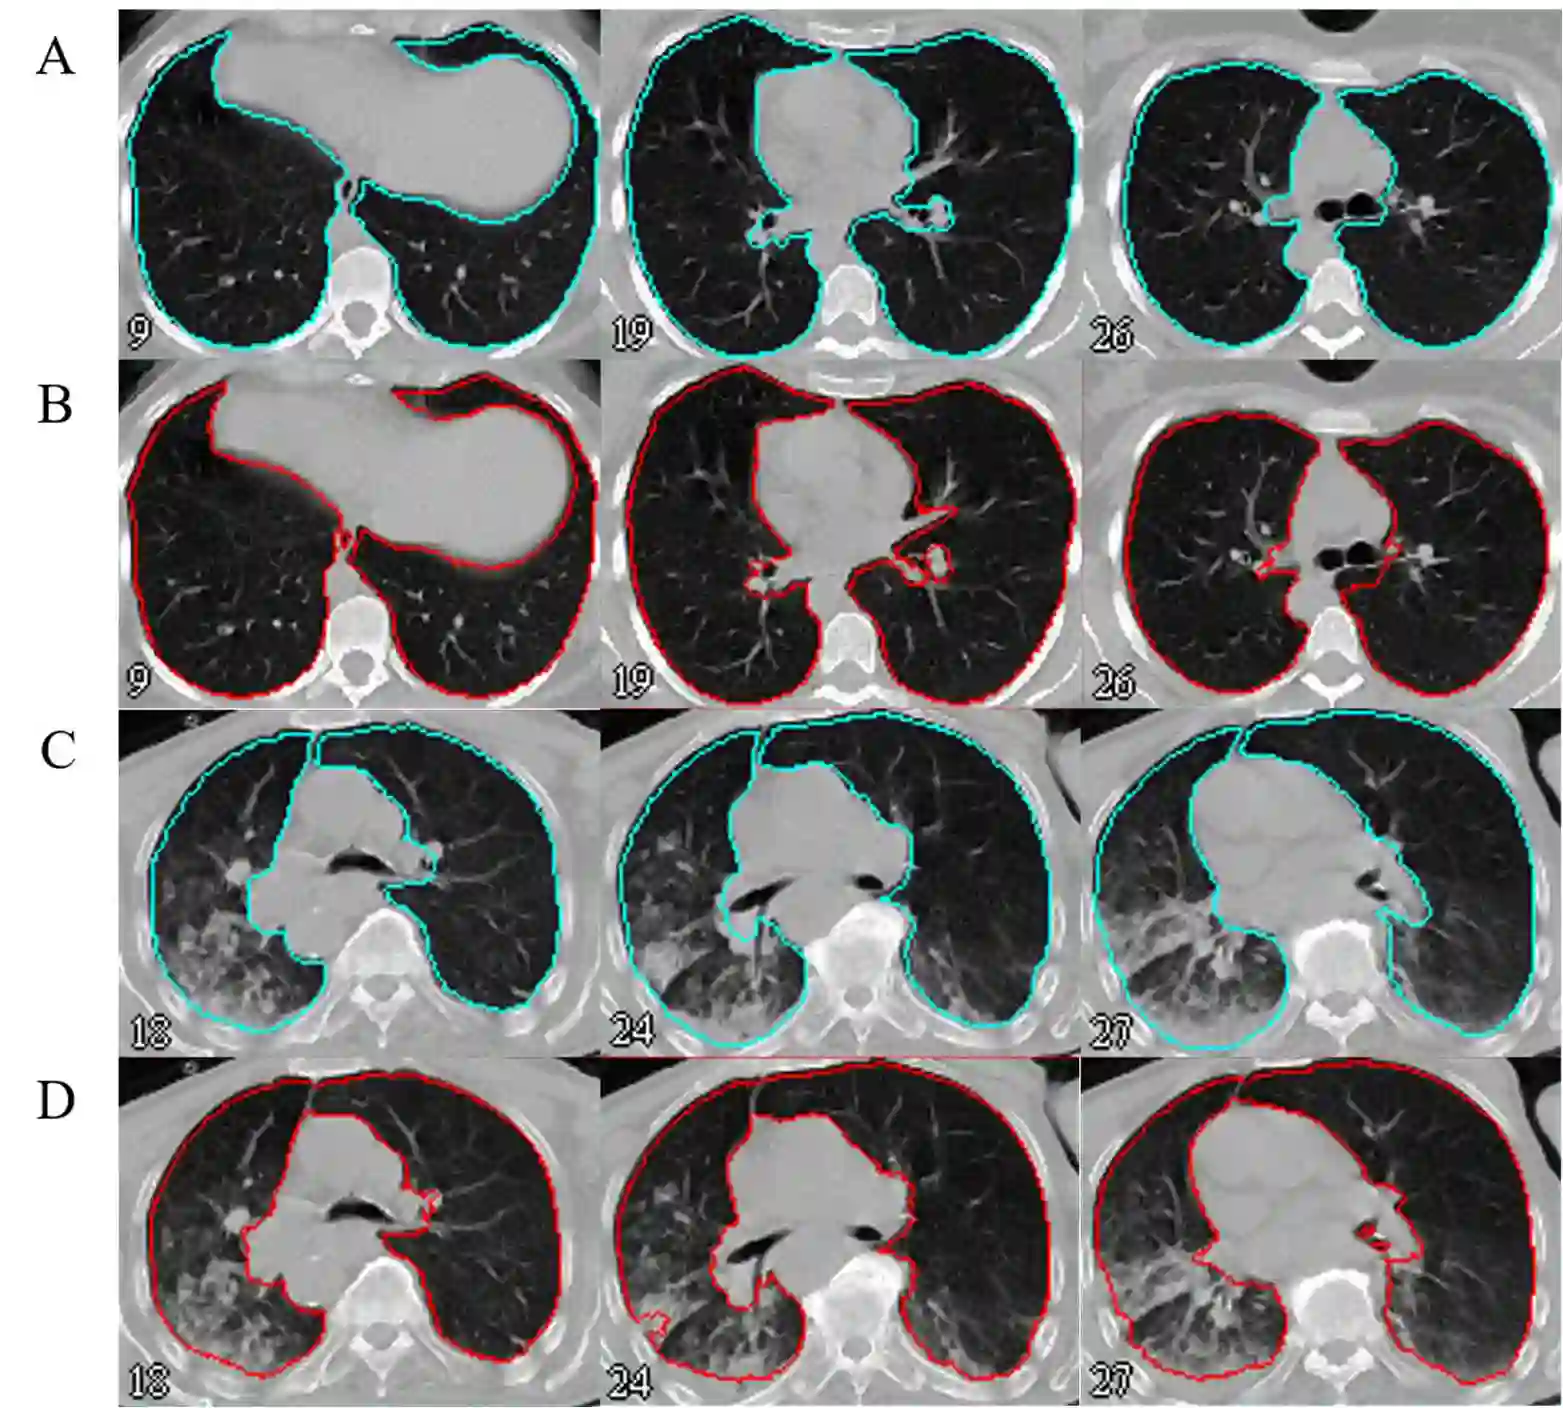

Automated semantic image segmentation is an essential step in quantitative image analysis and disease diagnosis. This study investigates the performance of a deep learning-based model for lung segmentation from CT images for normal and COVID-19 patients. Chest CT images and corresponding lung masks of 1200 confirmed COVID-19 cases were used for training a residual neural network. The reference lung masks were generated through semi-automated/manual segmentation of the CT images. The performance of the model was evaluated on two distinct external test datasets including 120 normal and COVID-19 subjects, and the results of these groups were compared to each other. Different evaluation metrics such as dice coefficient (DSC), mean absolute error (MAE), relative mean HU difference, and relative volume difference were calculated to assess the accuracy of the predicted lung masks. The proposed deep learning method achieved DSC of 0.980 and 0.971 for normal and COVID-19 subjects, respectively, demonstrating significant overlap between predicted and reference lung masks. Moreover, MAEs of 0.037 HU and 0.061 HU, relative mean HU difference of -2.679% and -4.403%, and relative volume difference of 2.405% and 5.928% were obtained for normal and COVID-19 subjects, respectively. The comparable performance in lung segmentation of the normal and COVID-19 patients indicates the accuracy of the model for the identification of the lung tissue in the presence of the COVID-19 induced infections (though slightly better performance was observed for normal patients). The promising results achieved by the proposed deep learning-based model demonstrated its reliability in COVID-19 lung segmentation. This prerequisite step would lead to a more efficient and robust pneumonia lesion analysis.